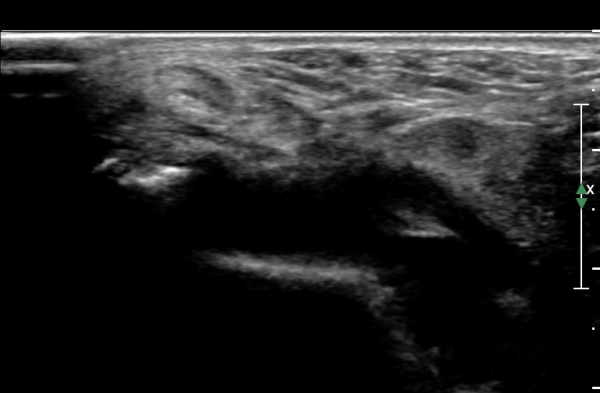

Á¾°ñºñ°ñÀδë Á¾´Ü¸é°Ë»ç¿¡¼­ °Å°ñÇϰüÀýÀÇ ¼ö¾×Àú·ù(Á¾°ñºñ°ñÀÎ´ë ½ÉºÎ ¼ö¾×Àú·ù)°¡

°üÂûµÈ´Ù(»çÁø 4).